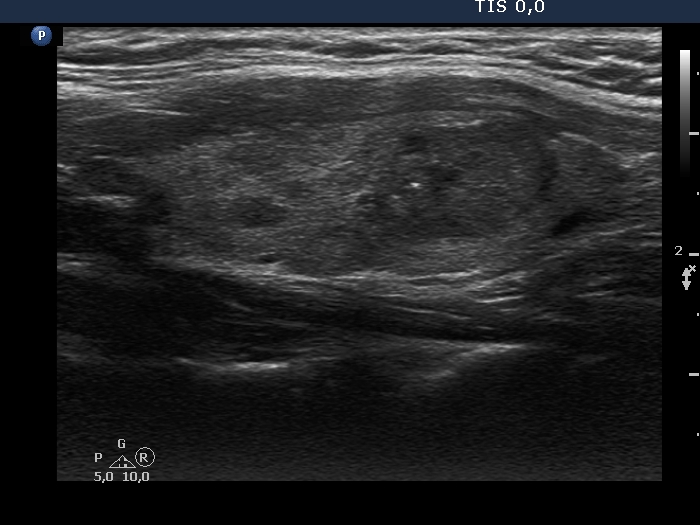

Second examination (second row of images):

Clinical presentation: The patient had no complaints.

Palpation: unchanged.

Functional state: euthyroidism (TSH 1.09 mIU/L).

Ultrasonography. The pattern remained unchanged.

Cytology resulted in Hashimoto's thyroiditis and suspicion of papillary cancer.

Total thyroidectomy was performed. Histopathology disclosed a T1b stage, encapsulated papillary cancer and Hashimoto's thyroiditis.

Comment. As a rule, we did not expect a malignant transformation of a benign nodule. The issue is the failure of FNA. In a nodule presenting suspicious ultrasound characteristics, repeat FNA is suggested even if the original cytological report was reassuring.